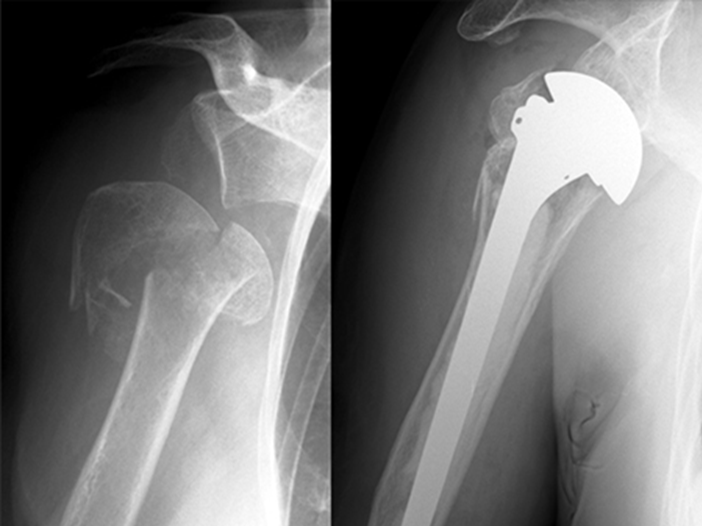

肩関節の重度の破壊や機能障害に対しては、人工肩関節全置換術(TSA)や、上腕骨頭のみを人工骨頭に置き換える人工骨頭置換術(HA)が有効な治療法です。これらの手術は、痛みの緩和や関節機能の改善を目的とします。

人工骨頭置換術(HA)

- 概要: 上腕骨の骨頭のみを人工骨頭に置き換える手術です。

- 適応: 上腕骨の骨頭部分のみが傷んでいる変形性肩関節症や、上腕骨近位部骨折などが主な適応となります。

- 目的: 上腕骨頭の破壊による機能障害を改善します。